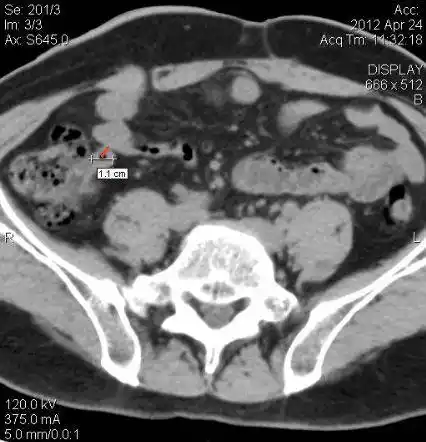

急性阑尾炎的ct表现